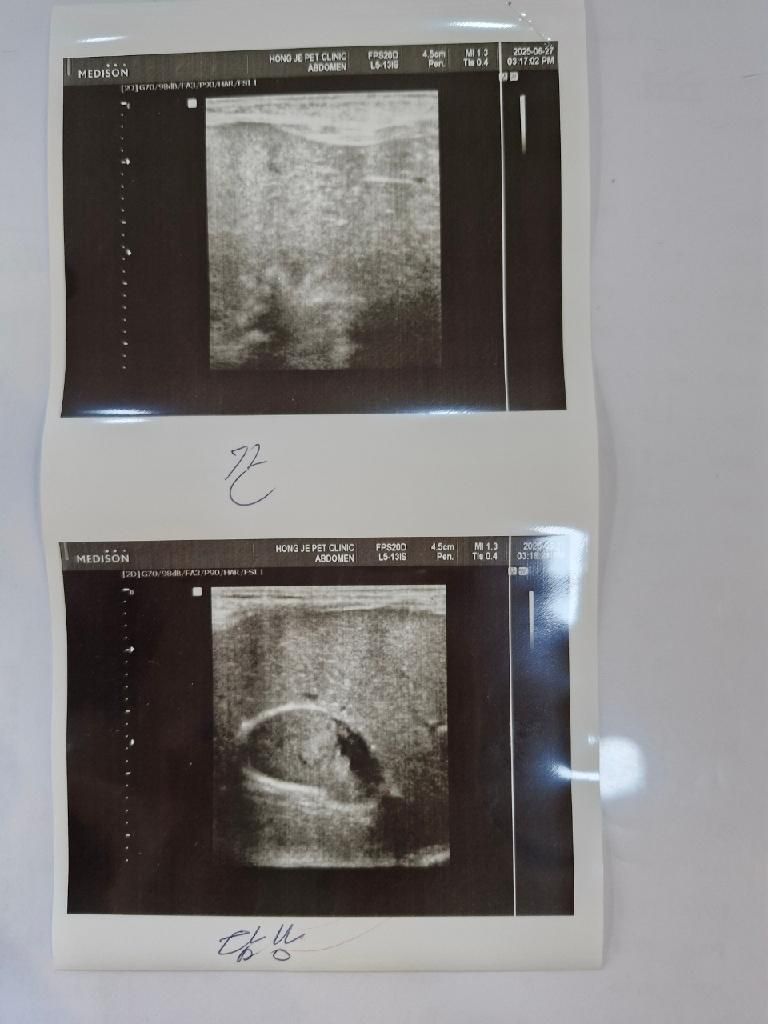

11살 강아지 담낭슬러지 우루사 약 복용양이 궁금합니다.

우루사 얼마나 먹이는게 맞을까요?

병원마다 하는말이 다 달라서 여기서도 물어봅니다

kg 당 4mg 먹이라는 A 병원

kg 당 10mg 먹이라는 B 병원

우루사 100mg 하루에 한알 반반 나눠먹이라는 C병원

대체 어느게 맞는걸까요??

세곳다 초음파 봤고 세곳다 자주 다니는 병원이고 다 자주 보는분들입니다